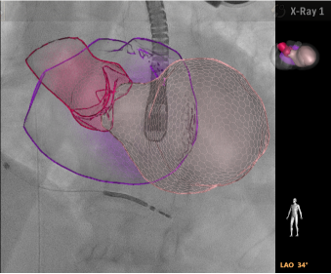

アンギオとエコーとのフュージョンでは,従来からのスマートフュージョン技術により,2Dエコー画像やカラードプラ,さらには3Dエコー画像との重畳表示,またSHD手技をナビゲートするための任意の組織へのマーカー機能があった。

今回,新たにバーチャルモデルによるAnatomical Intelligenceモード(解剖学的知能モード)を搭載。自動でセグメンテーションすることで,心室や,心房全体および僧帽弁や左心耳などのアンギオ画像では確認することができない動的組織モデルとアンギオ断面とのフュージョンも容易になり,デバイスが目的の留置位置に存在するか,カテーテルの先端による心臓壁穿孔のリスクがないかなど,リアルタイムにアンギオ画像とエコー画像が一体となり画期的な機能が追加され,さらに直感的に視覚化することが可能となった。

新たに搭載されたバーチャルモデルによるAnatomical Intelligenceモード(解剖学的知能モード)

アンギオの集中管理モニター上に表示